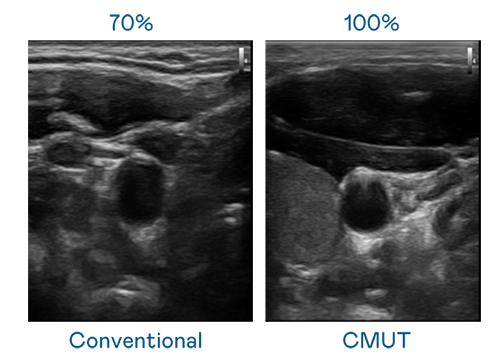

CMUT 技术是一种用电容式微机电元件来产生超音波讯号的技术。与传统 PZT 压电式技术相比,CMUT 频宽增加 30%,更宽频的超音波讯号让影像解析度大幅提升,是实现高影像品质医疗超音波扫描、促进精准医疗发展的关键技术。

大频宽带来超清晰影像

超音波影像的解析度高低,首先取决于探头能发出的讯号频宽。z6mg·人生就是博 CMUT 可提供高清晰的超音波讯号,提供高频宽、高灵敏度、影像纹理细节更高的超音波影像,协助医护人员缩短影像判读时间及利用精准的医疗影像进行诊断。